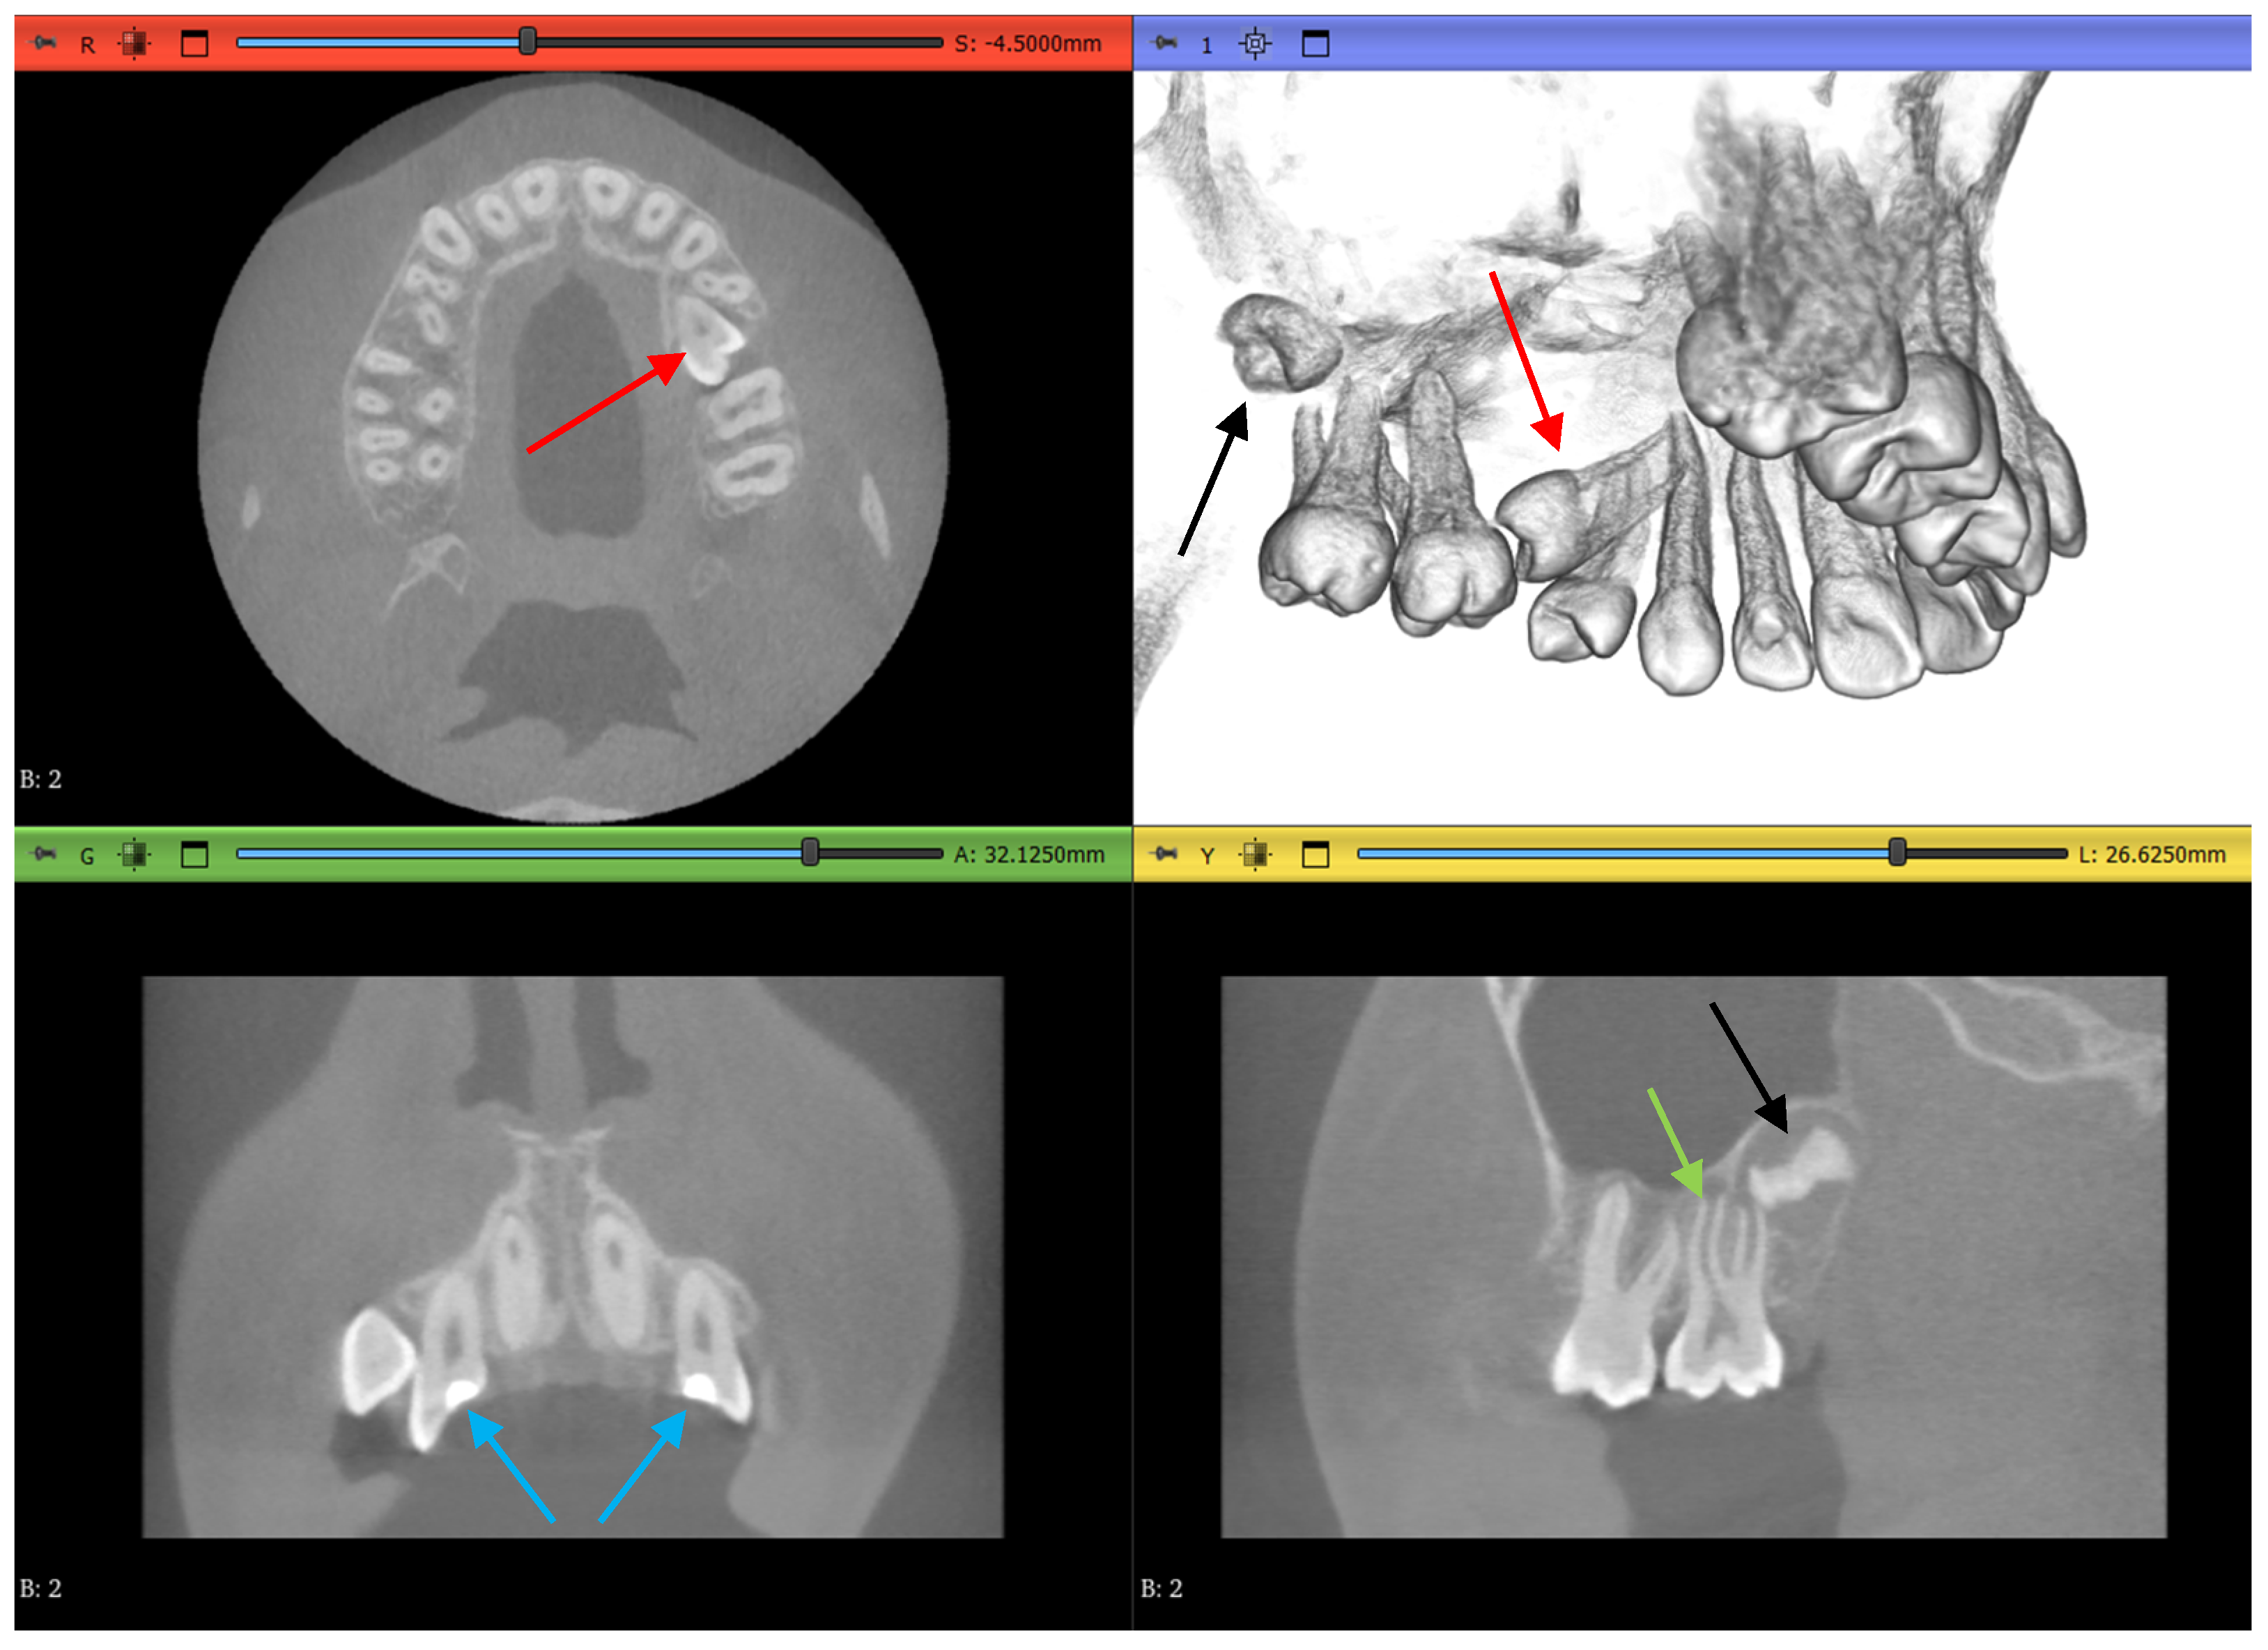

Dataset 2 is slightly more challenging, as it does not contain mandibular teeth. Figure 5 shows that the maxillary teeth are newly erupted with open apexes, as shown by a green arrow, have restorative operations shown by blue arrows, an impacted second premolar, as shown by red arrows, and an unerupted third molar, as shown by black arrows.

Figure 5.

Dataset 2 of the study showing open apexes by a green arrow, restorations by blue arrows, impacted molar by red arrows, and unerupted molar by black arrows.

Dataset 3 presents the most challenging obstacle to the workflows, as it includes braces, and the maxillary second molar chosen has 4 roots instead of the more common 3-root configuration, as shown in Figure 6 by the red arrow.

Figure 6.

Dataset 3 of the study with a red arrow pointing to the 4-rooted maxillary second molar.